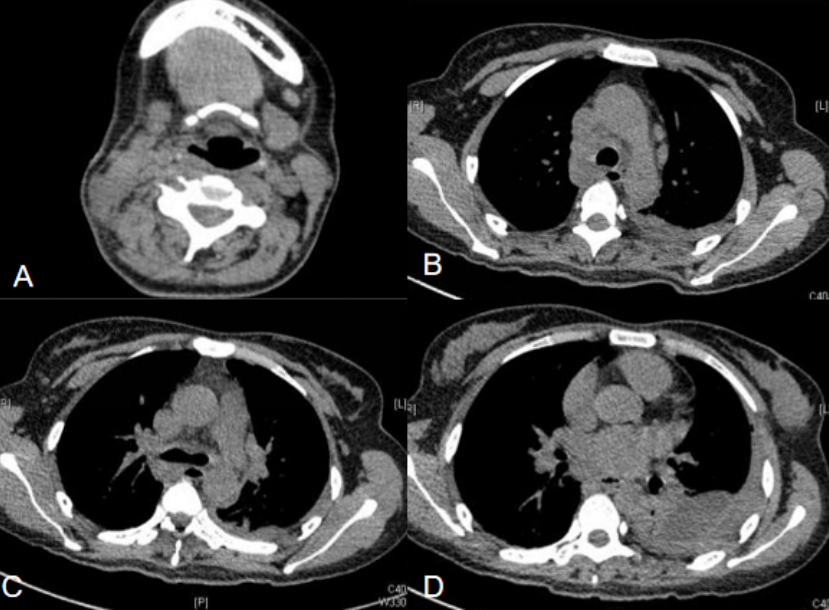

患者于2012年3月12日无明显诱因下出现咽喉部痒痛、吞咽困难,自服“感冒颗粒”1袋后症状无好转,于3月13-19日在当地卫生所抗感冒治疗(具体诊断不详,用药不详)。期间患者右颈部肿大,发热,体温最高40℃。于3月19日转当地医院普外科继续治疗。颈部B超示右侧颈部低回声,考虑炎性可能。期间给予“头孢他啶+氨曲南”抗感染治疗(其他治疗不详),白天用药后退热,夜间再度发热,体温在38~39℃。3月21日患者出现胸闷,伴有咳嗽,咳少量白色黏痰,给予止咳对症治疗,效果不佳。3月25日右颈部肿块较前明显,颈部B超示右侧颈部脓肿伴液化。为求进一步治疗,就诊于我院急诊科,3月26日颈胸部CT示右侧颈部脓肿,纵隔脓肿,左下肺浸润影,左侧胸腔包裹性积液(图1)。给予左侧胸腔闭式引流术。3月28日拟“左侧脓胸”收入我科重症监护病房加强监护。病程中体力下降,食欲下降,睡眠欠佳,近半月体重减轻5 kg,大便正常,排尿正常。既往体健,近期无拔牙、龋齿发炎等口腔问题,无外伤史。

图1 颈胸部CT(2012-03-26)

注:A为右侧颈部脓肿(箭头所指);B为纵隔内脓肿;C、D为左侧胸腔包裹性积液